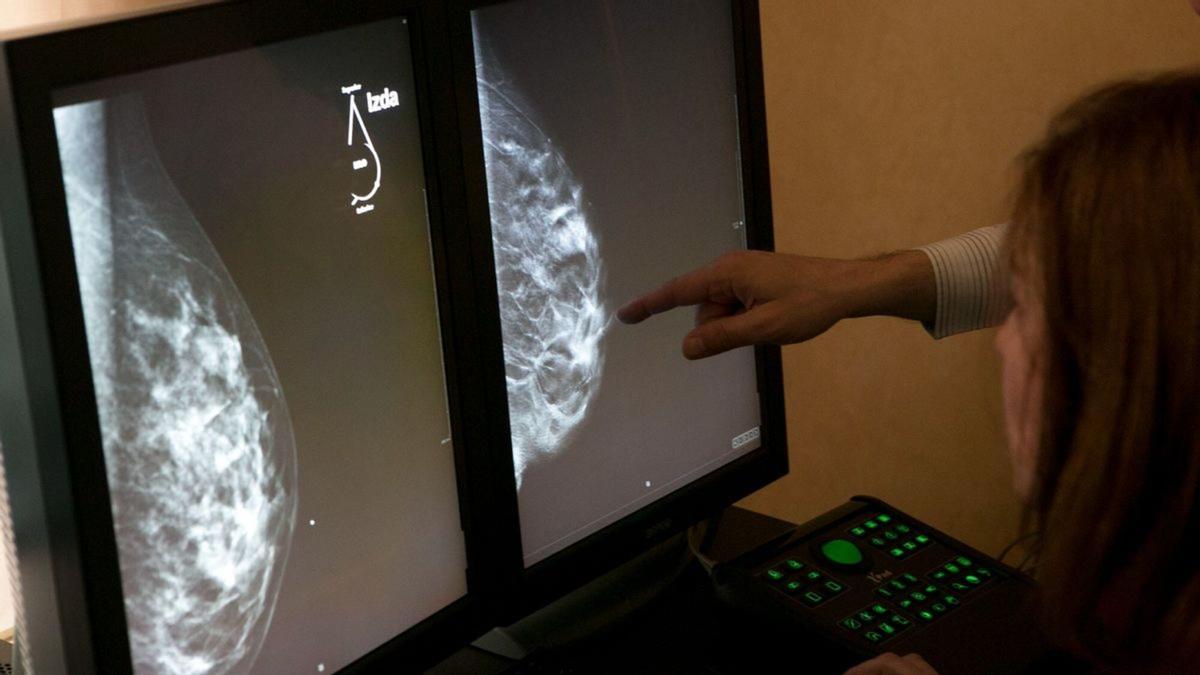

Una imagen de una prueba de mamografía. / Levante-EMV

El sindicato médico CESM ha criticado que la Conselleria de Sanidad haya anulado las segundas lecturas que se hacen de las mamografías del cribado de cáncer de mama (que se hace a las valencianas de 45 a 75 años cada dos años para prevenir este tipo de tumor) por falta de radiólogos. Es decir, a partir de ahora, las pruebas solo serán vistas e informadas por un radiólogo y no por dos diferentes, método que se venía utilizando para evitar errores diagnósticos.

Desde CESM recuerdan que las dobles lecturas son una de las características del programa de prevención de cáncer de mama (que lleva 30 años en marcha) ya que ayudan a reducir "de manera significativa los falsos diagnósticos, tanto en positivo como en negativo" y que se han eliminado incluso en aquellas "unidades de prevención que contaban con radiólogo segundo lector".

Y es que, hasta ahora, en las mamografías que se hacían dentro de este programa siempre se informaban dos veces por dos radiólogos distintos. Si había consenso entre los dos al respecto de la prueba no había problema pero si había discrepancia entre los informes, se hacía una nueva valoración para confirmar el diagnóstico y evitar que se pudiera obviar algún cáncer incipiente. Esta forma de trabajar se abandonó a principios de marzo tras una comunicación interna de Sanidad a las unidades de prevención al no existir "suficiente personal" ligado al programa.